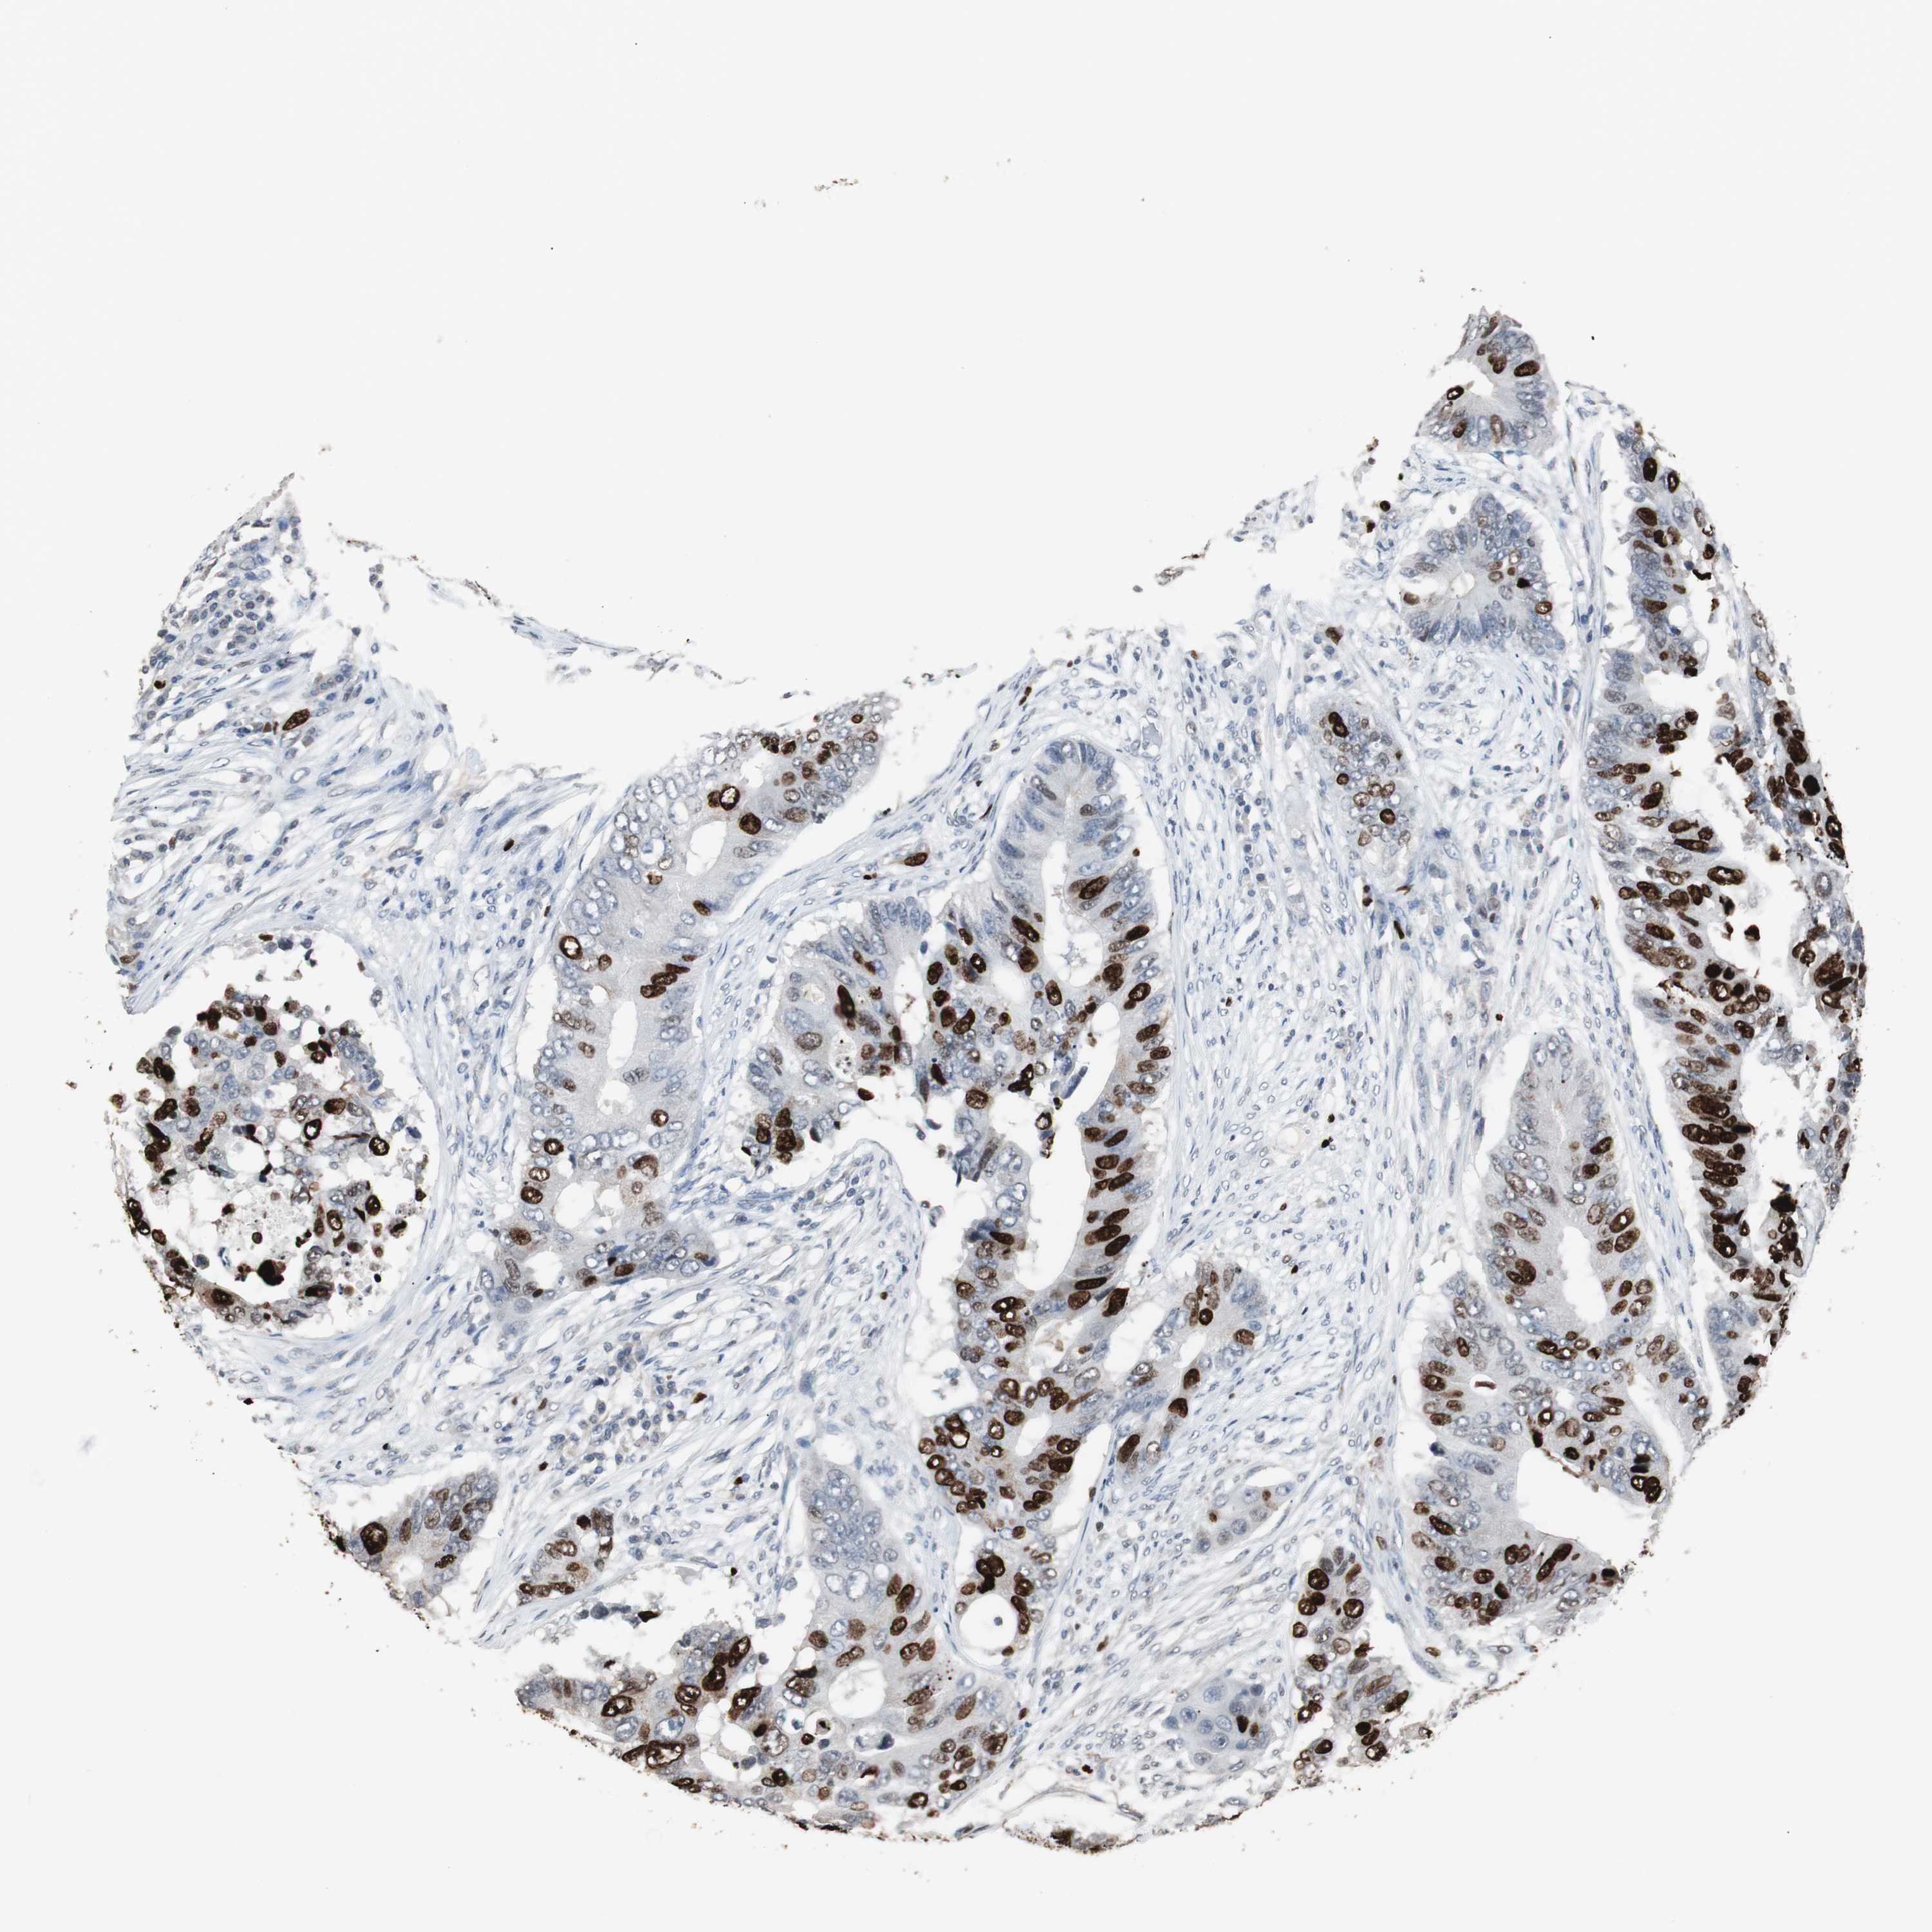

CANCER COLORECTAL CANCER Show tissue menu

Colorectal cancer

Colon adenocarcinoma